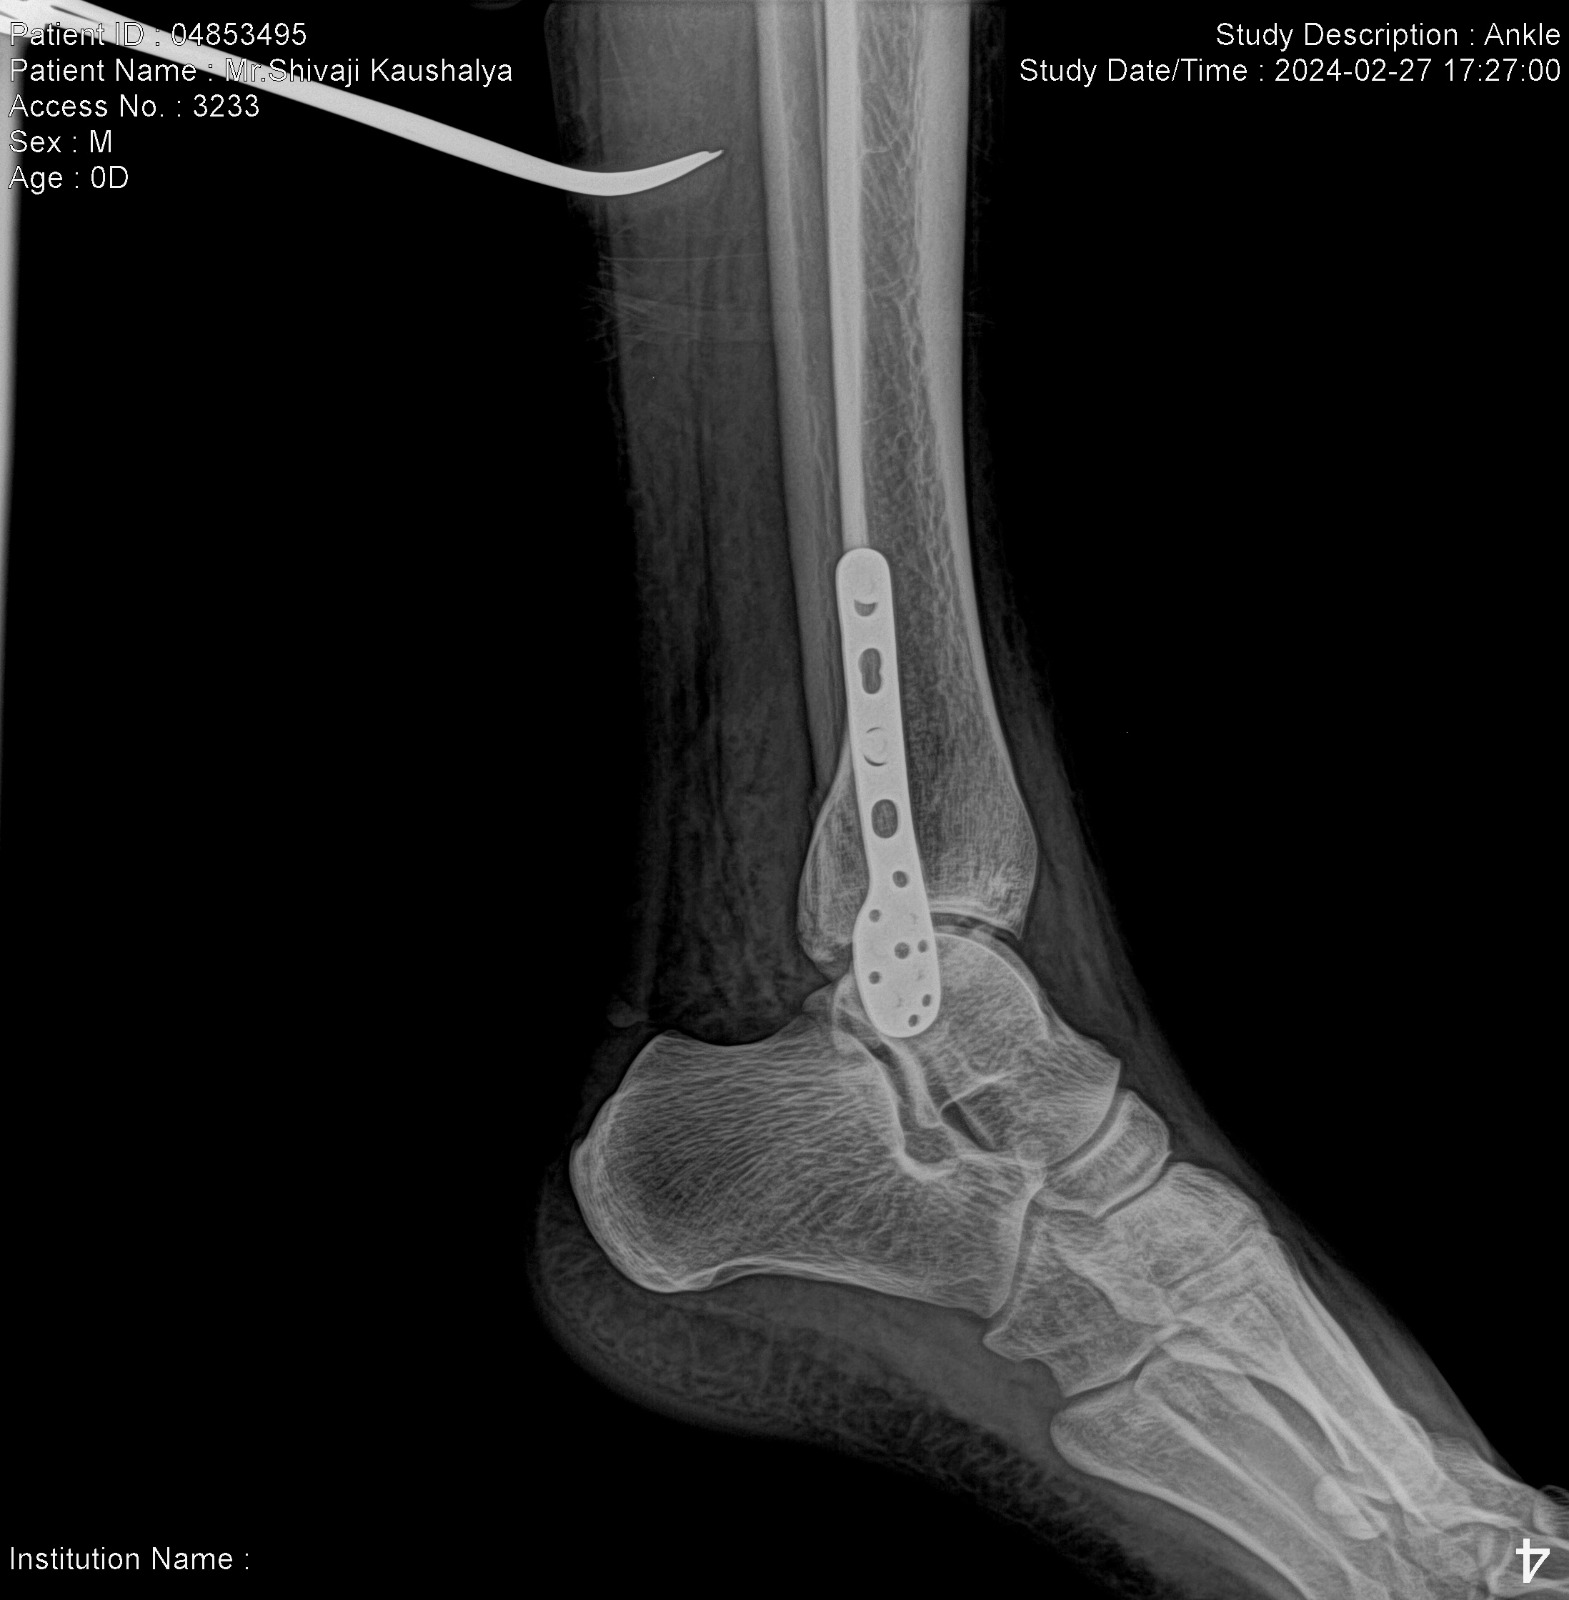

High-resolution imaging solutions emerged as a beacon of hope, offering unprecedented clarity and precision in medical imaging. These advanced systems are designed to capture minute details with astonishing accuracy, allowing healthcare professionals to identify and analyze even the subtlest of abnormalities. For Dr. Mehta, this meant the ability to provide definitive answers to his patients, alleviating their fears and uncertainties.

Consider the case of Priya Sharma, a 45-year-old mother of two from Chennai, who had been experiencing persistent headaches and dizziness. Despite undergoing numerous tests, her condition remained undiagnosed, leaving her family in a constant state of worry. It wasn't until she was referred to a facility equipped with high-resolution imaging solutions that the true cause of her symptoms—a small, previously undetected aneurysm—was discovered. Thanks to the precision of the imaging, Priya received timely intervention, and her recovery has been nothing short of miraculous. Stories like Priya's are becoming increasingly common as more healthcare providers embrace this cutting-edge technology.